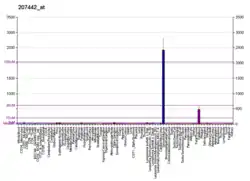

Genetics

The gene for G-CSF is located on chromosome 17, locus q11.2-q12. Nagata et al. found that the GCSF gene has four introns, and that two different polypeptides are synthesized from the same gene by differential splicing of mRNA.[10]